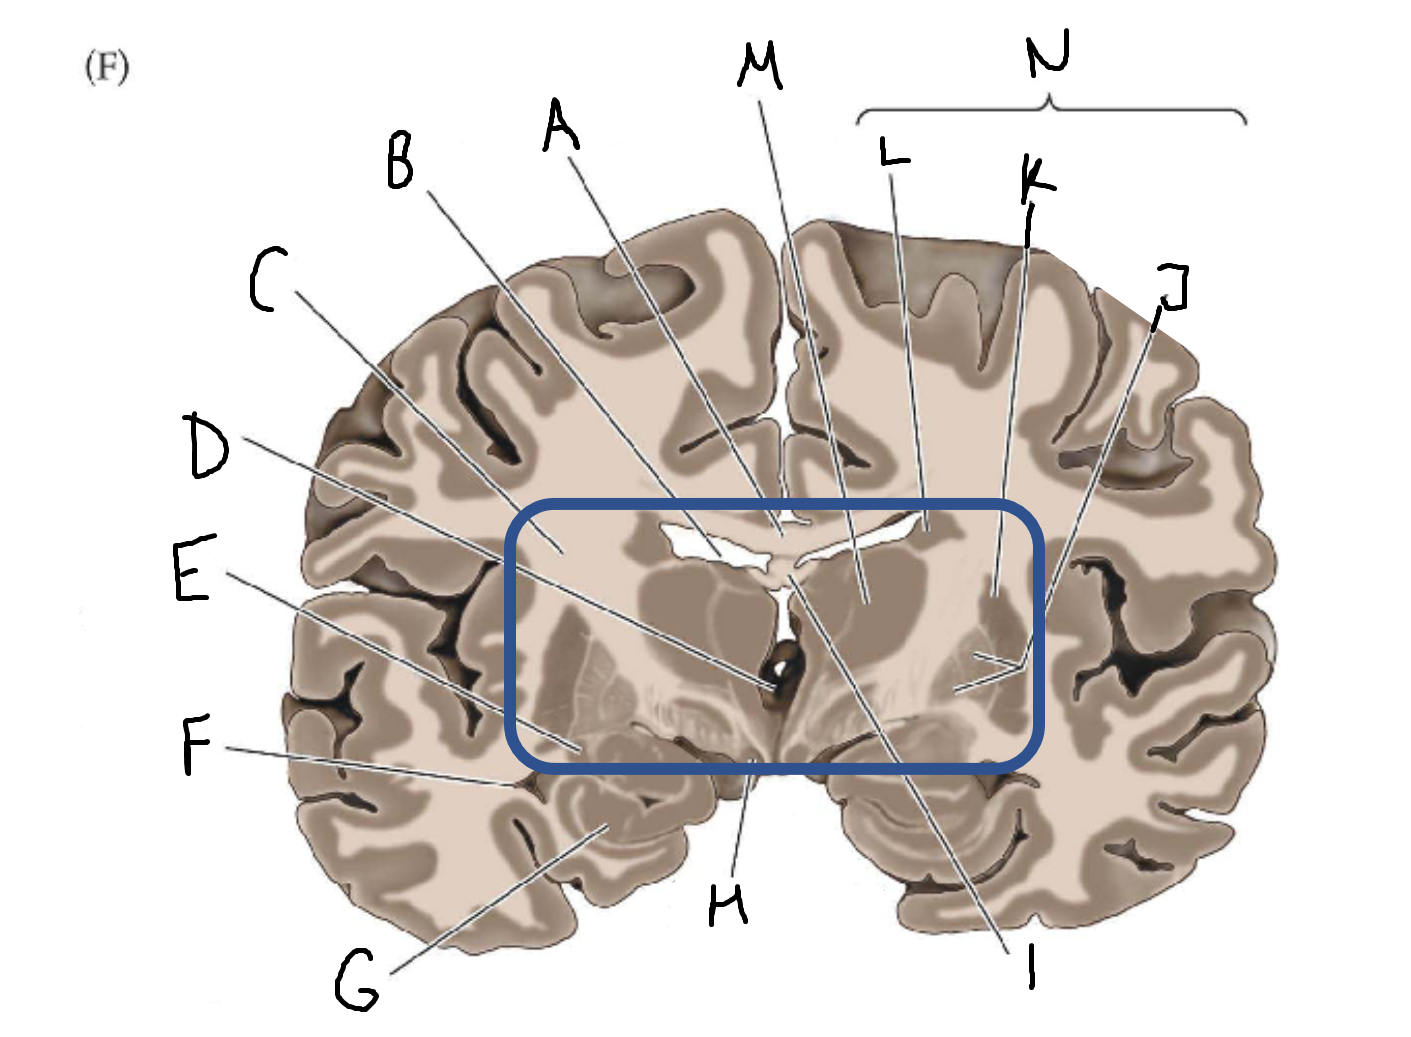

A

corpus callosum

B

lateral ventricle

C

internal capsule

D

third ventricle

E

tail of caudate nucleus

F

lateral ventricle

G

hippocampus

H

mammillary body

I

fornix

J

globus pallidus

K

putamen

L

caudate

M

thalamus

N

basal ganglia